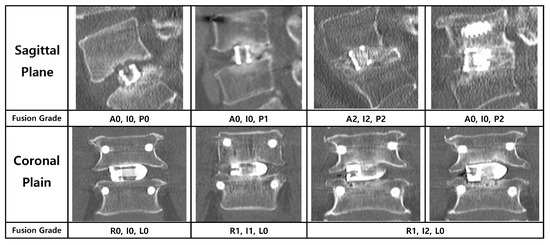

The primary endpoint of this study was the radiological fusion rate, assessed using multi-planar reconstructed CT images obtained at 3, 6, 12, and 24 months postoperatively. To provide a detailed analysis, the location of new bone formation was classified based on its position relative to the cage. On sagittal plane images, the locations were defined as (A) anterior to the cage, (I) inside the cage, and (P) posterior to the cage. On coronal plane images, they were defined as (L) left of the cage, (I) inside the cage, and (R) right of the cage (Figure 4).

The degree of fusion was evaluated using a simplified three-grade grading system. While the classification described by Bridwell et al. is a foundational standard, we adopted a more distinct definition for clarity, inspired by the methodology of a prior study on PLIF fusion rates [12]. Fusion was graded as follows: Grade 0 (Non-union) was defined as the complete absence of bone growth; Grade 1 (Partial Fusion) as the presence of bone growth without a continuous bone bridge connecting the superior and inferior vertebral bodies; and Grade 2 (Complete Fusion) as the formation of a continuous, solid bone bridge. For the final analysis, Grade 2 was considered a successful fusion (Figure 5).

Figure 5. Radiological criteria and representative CT images for the three-grade fusion grading system. The figure illustrates the grading system used to assess bony fusion on multi-planar CT images, with representative examples provided for both the sagittal (left column) and coronal (right column) planes. Fusion was categorized into three grades: Grade 0 (Non-union) was defined as the complete absence of new bone formation; Grade 1 (Partial Fusion) as the presence of bone growth without a continuous bridging trabecular bone between the vertebral bodies; and Grade 2 (Complete Fusion) as the formation of a continuous, solid bone bridge. For the purpose of the final analysis in this study, only Grade 2 was considered a successful fusion.